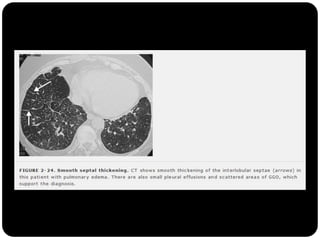

Padrão Alveolar  Opadrão alveolar ou do espaço aéreo é caracterizado por opacidade homogênea.  Ocorre pela ocupação do espaço aéreo por outras substâncias que não o ar: exsudato nas pneumopatias, transudato nos edemas pulmonares, sangue, células neoplásicas e materiais estranhos no caso de aspiração (ex. aspiração de óleo mineral)

Vidro fosco  Opacidadeobservada naTC, pode ser decorrente tanto de alteração do espaço aéreo quanto do interstício.  Alvéolos ou interstício ocupados parcialmente por processo patológico (líquido, células, exudato); Resoluação daTCAR não é suficiente para definir a imagem;